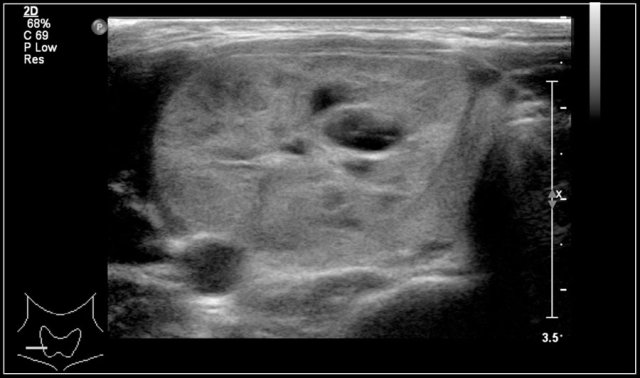

Here an image of a 16-year-old girl with hyperthreoidism.

A diffusely enlarged thyroid gland is seen with hyperemia.

The final diagnosis was Graves disease.

She was treated with I-131.